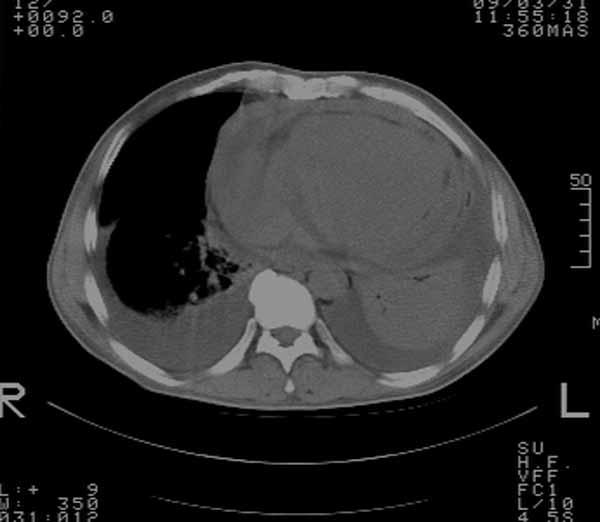

以下是引用余辉在2009-3-31 18:43:00的发言:[br]肺水肿,双侧心腔积液,心包积液,心影增大,疑似心衰

以下是引用wangyong1977在2009-3-31 20:46:00的发言:[br]肺水肿,双侧胸腔积液,心包积液,心影增大,疑似心衰 [br]

以下是引用宇宙ct在2009-3-31 18:57:00的发言:[br]肺水肿,双侧心腔积液,心包积液,心影增大,疑似心衰 [br] [br]